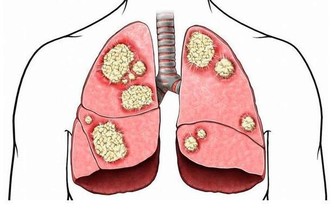

事實上,腸道對人體來說就好像“下水道”,只要是負責人體一些垃圾毒素的排泄。如果一旦發生堵塞,糞便長期滯留在腸道,就很有可能引起急性或者慢性便秘。這個時候,人體的代謝所產生的廢物和毒素會被再次吸收,容易出現精神萎靡、色斑、痤瘡、腹痛腹脹的多種症狀,毒素還會刺激腸壁,造成腫瘤發病率的增高。因此,如果感到自己排便次數有明顯減少,或者是糞便乾結髮硬,排出困難時,就需要特別注意了。

部分引起慢性便秘的病因危險性很大,如肛門損傷、腸梗阻、腸嵌塞或潰瘍、腸道惡性腫瘤等,此時最好及時到專科門診就診,以免延誤疾病診治。